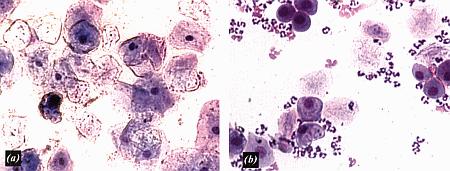

Фиг. 2.2.

Вагинальные выделения кошки (а). Выделения, типичные для фазы эструса. Большая часть клеток представляет собой безъядерные кератинизированные клетки или клетки с пикнотическим ядром. Присутствуют промежуточные клетки (b). Выделения, характерные для метэструса, — «течки», иногда наблюдаемой у кошек в конце эструса. Присутствуют поверхностные и промежуточные клетки, повышено содержание лейкоцитов. Этот короткий метэструс наблюдается в течение 24–48 часов (см. Приложение)